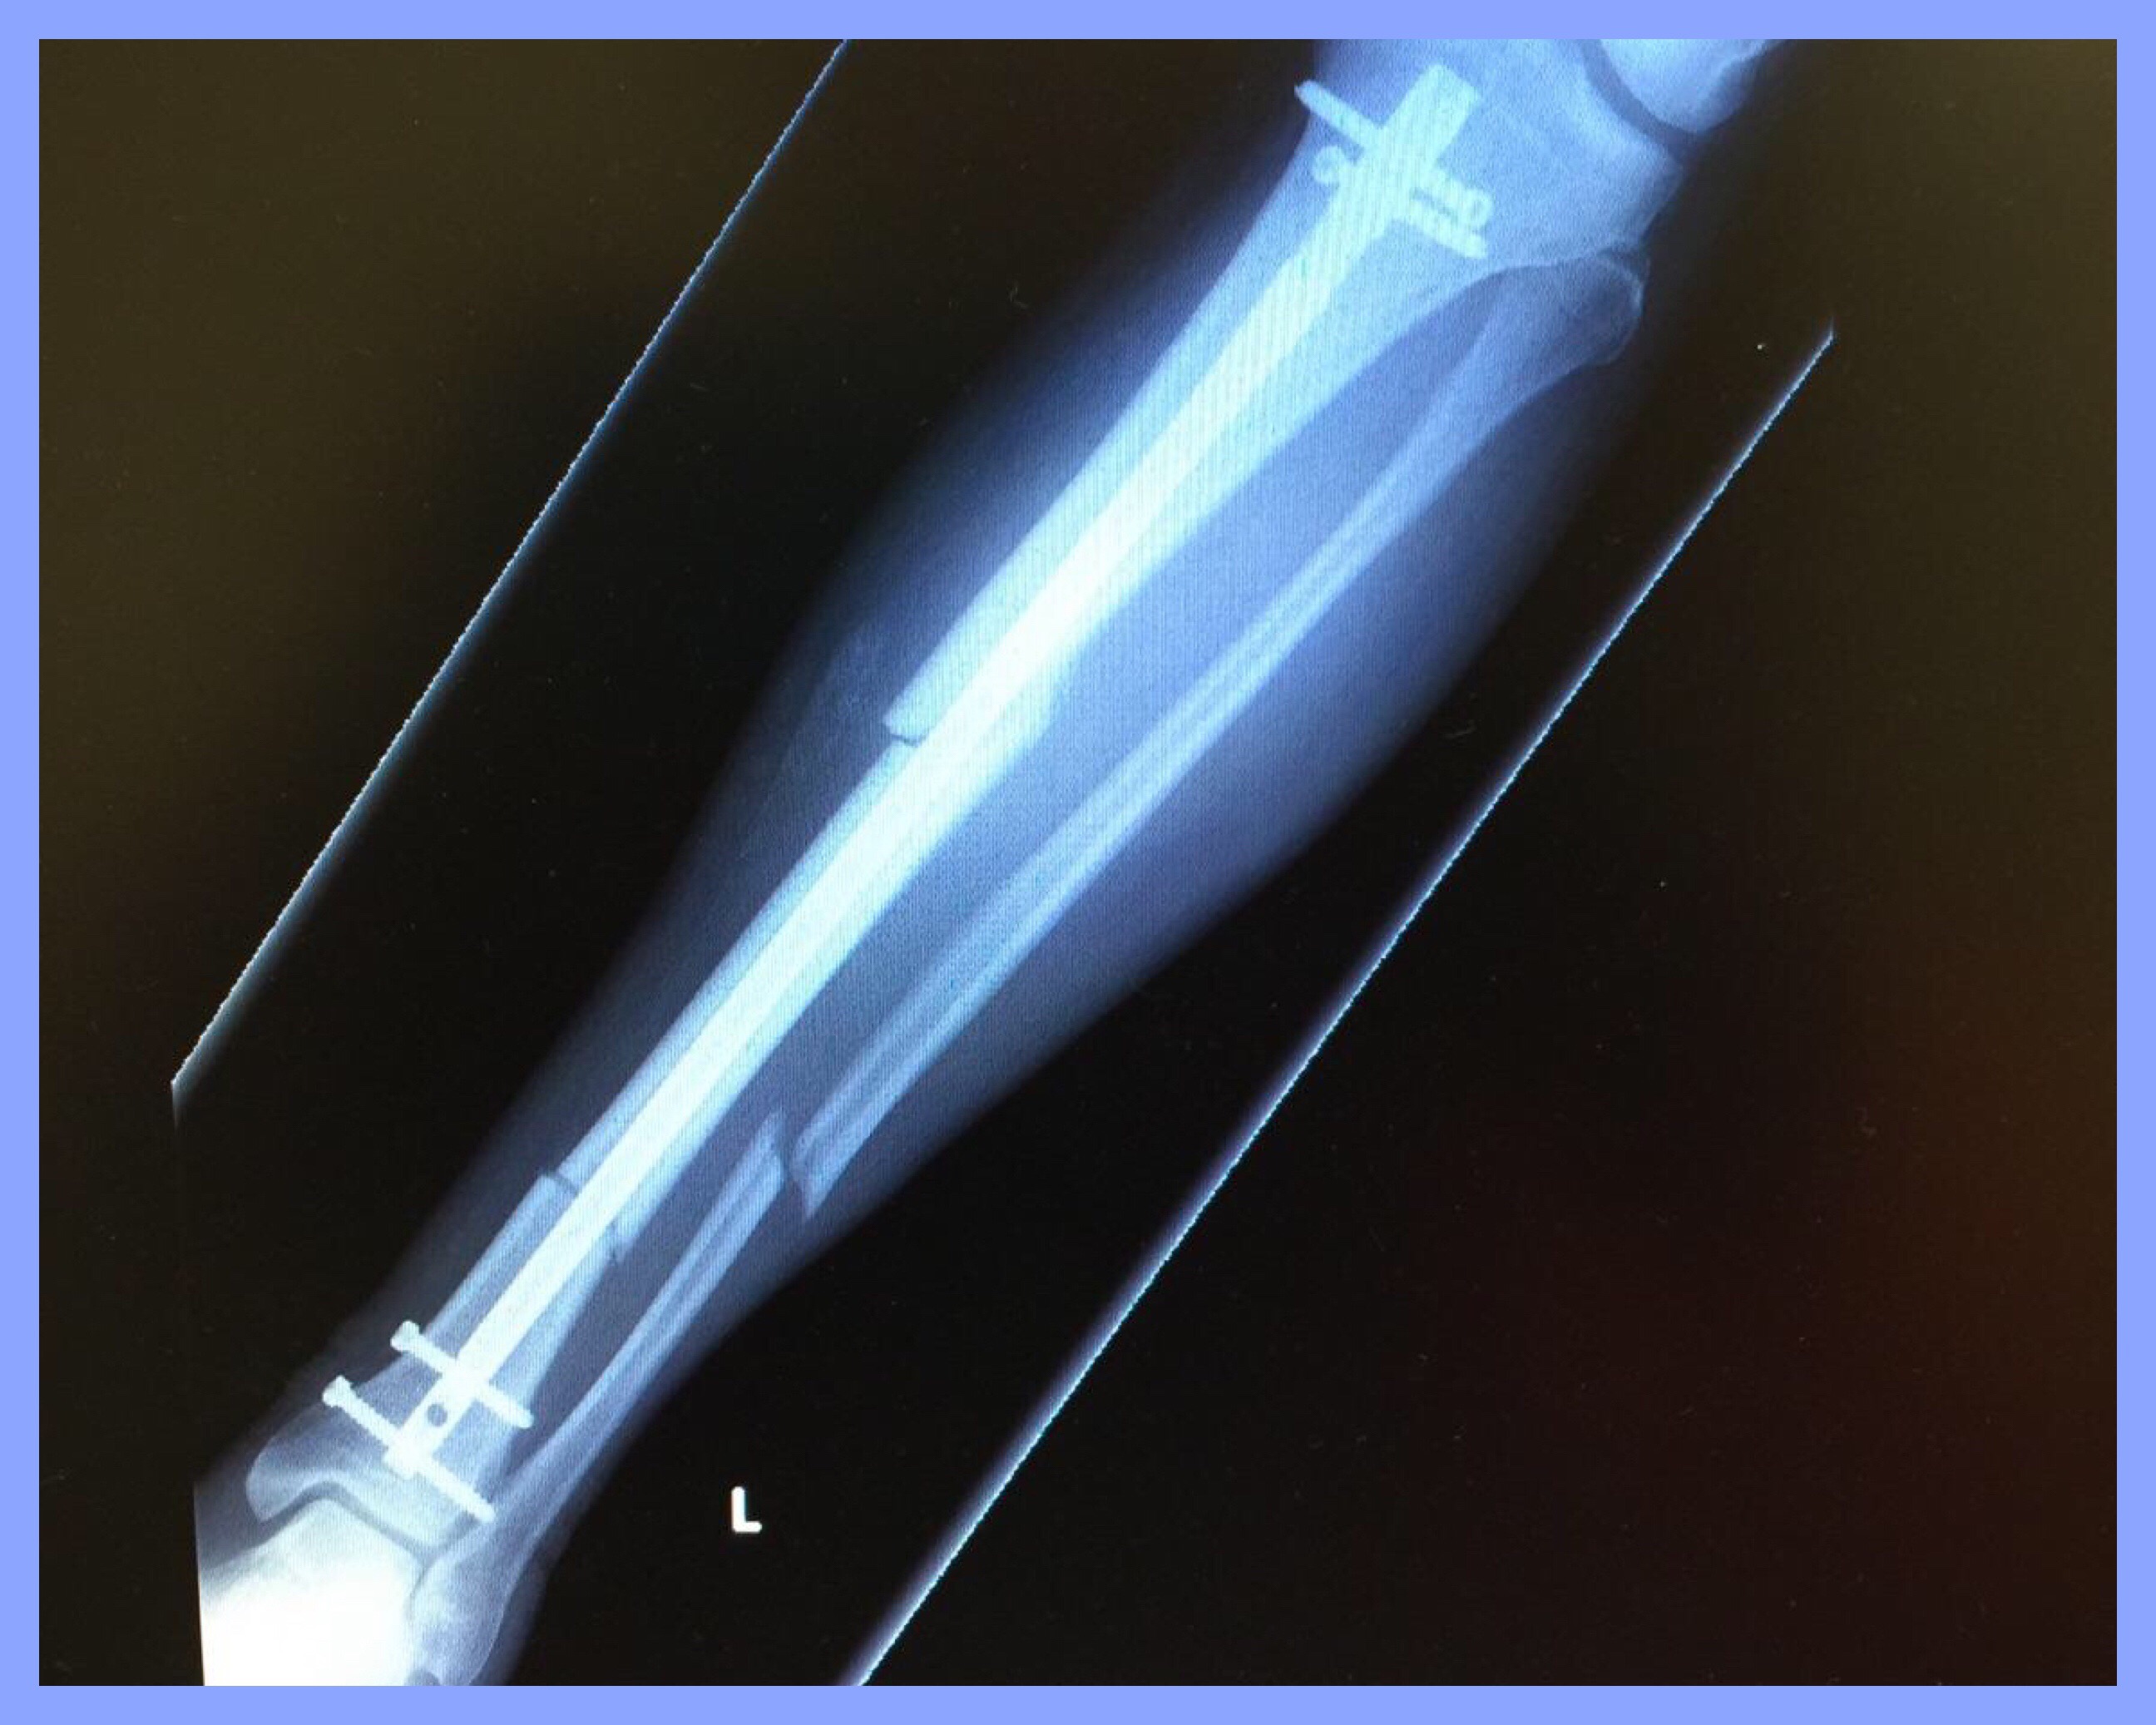

The impact broke my left lower leg in three places and knocked me to the pavement.

After 8 hours in the ER and 2 hours of surgery, I went home the next afternoon with the titanium rod and screws you see below. The hardware is permanent.